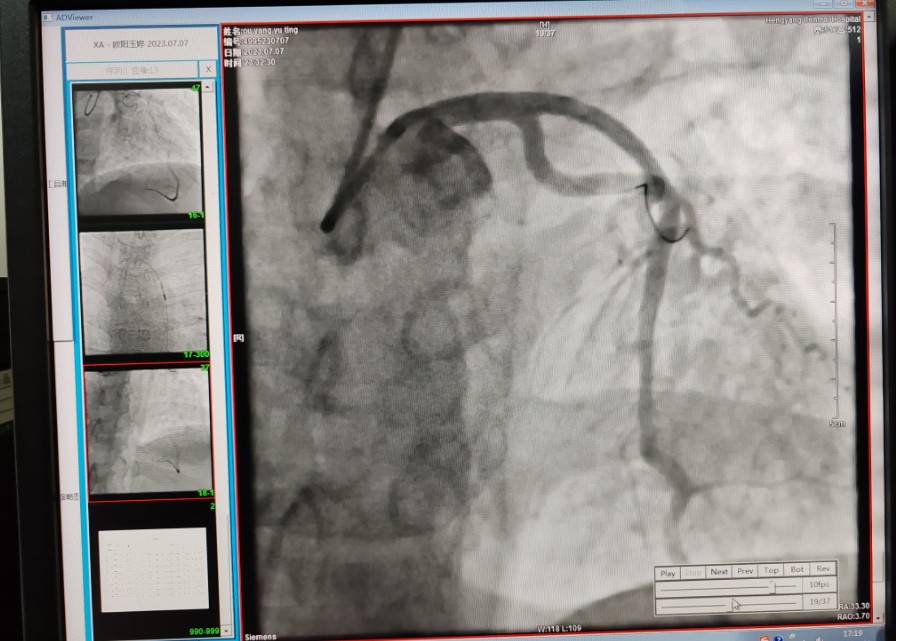

22:29分患者經(jīng)院內(nèi)綠色通道送達(dá)導(dǎo)管室,手術(shù)由雷剛副主任醫(yī)師主刀,楊繼賀副主任醫(yī)師為第一助手,介入技師及護(hù)士密切配合,聞?dòng)嵍鴣淼内w慶禧主任醫(yī)師坐鎮(zhèn)協(xié)調(diào)指揮。22:37分手術(shù)開始,冠脈造影顯示心臟上最重要的一條冠狀動(dòng)脈-前降支開口齊頭閉塞,血管粗大且血栓高負(fù)荷,非常考驗(yàn)介入術(shù)者的手術(shù)能力,一旦發(fā)生冠脈無復(fù)流或操作不慎血栓帶入回旋支導(dǎo)致循環(huán)崩潰,病人幾乎無生還希望;此時(shí),患者手術(shù)臺上仍持續(xù)胸痛,且血氧飽和度在高流量吸氧狀態(tài)下不到80%,雷剛副主任醫(yī)師一方面指揮鎮(zhèn)靜鎮(zhèn)痛及抗心衰治療,一方面緊急啟用IABP(主動(dòng)脈球囊反搏),然后精細(xì)操控細(xì)如發(fā)絲的介入導(dǎo)絲迅速通過病變,并予冠脈球囊擴(kuò)張、冠脈內(nèi)溶栓、抗痙攣藥物使用、植入冠脈支架,最終成功開通“罪犯”血管,且無手術(shù)并發(fā)癥發(fā)生,整個(gè)過程張弛有度、快慢結(jié)合、一氣呵成?;颊咝g(shù)后胸痛明顯好轉(zhuǎn),血氧飽和度上升至96%,術(shù)后1天轉(zhuǎn)出監(jiān)護(hù)病房,第3天拔出IABP,目前已康復(fù)出院。